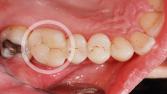

Zementiertes Keramikoverlay: Die individuell angefertigte Keramikfüllung wird mit einem speziellen Zement dauerhaft im Zahn verankert, sodass sie perfekt sitzt und belastbar ist.

Keramikoverlay:

Ein Keramikoverlay bedeckt grössere Zahndefekte. Es wird eingesetzt, wenn noch genug Zahnhartsubstanz vorhanden ist und noch kein Zahnersatz in Form von einer Krone nötig ist.